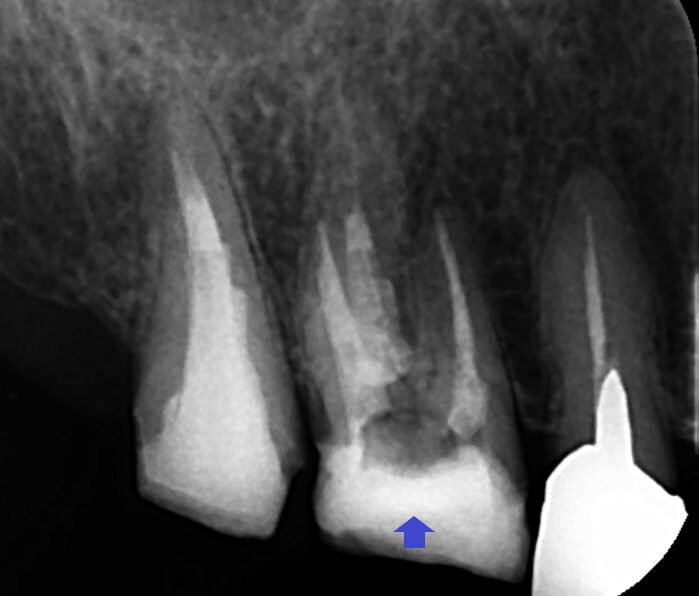

膿を改善するために精密再根管治療を行いました。顕微鏡下で近心頬側根の根管内を観察したところ、根管にはフィンと呼ばれる筋状の根管形態がみられ、そこに神経の死骸が残存していました。このフィンは、通常の根管治療では限界があり処置できないことが多いです。しかし、マイクロスコープにて拡大し明るい環境下で治療を行うことにより処置できていない部分を発見することができます。根管に取り残された神経の死骸が腐敗し、感染が根管に拡がって膿ができている可能性が高いので、フィンを削除し根管を隅々まで清掃後、根管充填しました。画像は、根管充填時のレントゲン写真です。